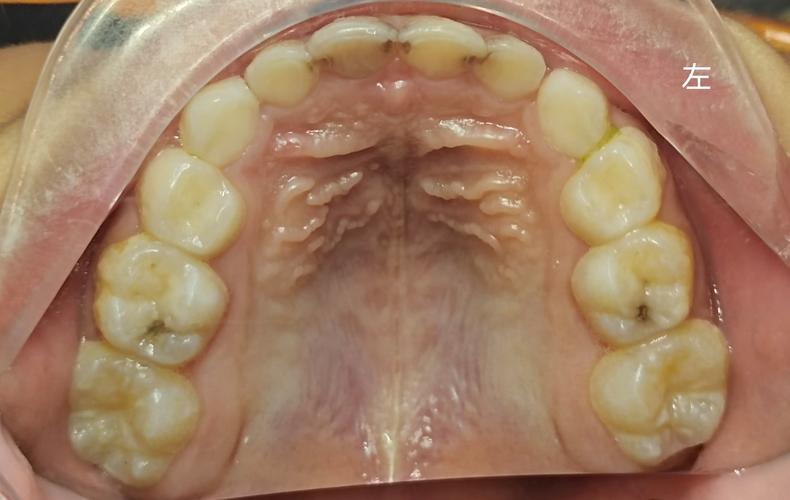

正畸治疗分为初期、调整期、保持期,不同阶段黏膜刺激的特点不同:

- 初期适应期(戴矫治器后1-2周):黏膜首次接触大量矫正装置,尚未建立适应性保护机制,易在托槽、弓丝对应部位出现局限性充血、糜烂,甚至形成“创伤性溃疡”,疼痛明显,影响进食。